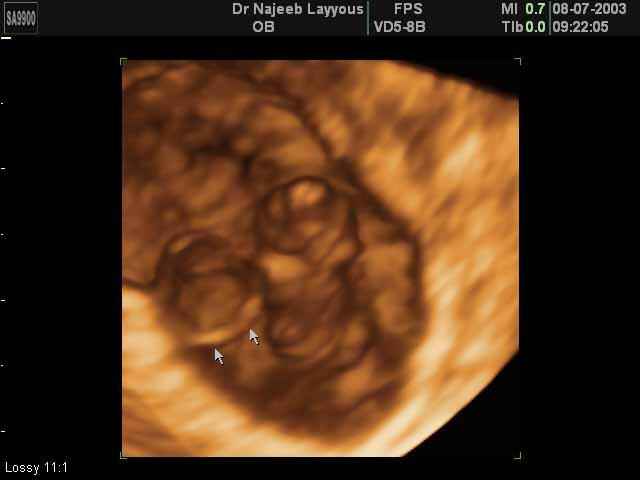

- First Trimester Ultrasound Photos

- The Clinical Advantages of 3D and 4D Ultrasound

- Definition and Features of Four Dimensional Ultrasound

- Uses of 4D Ultrasound scan